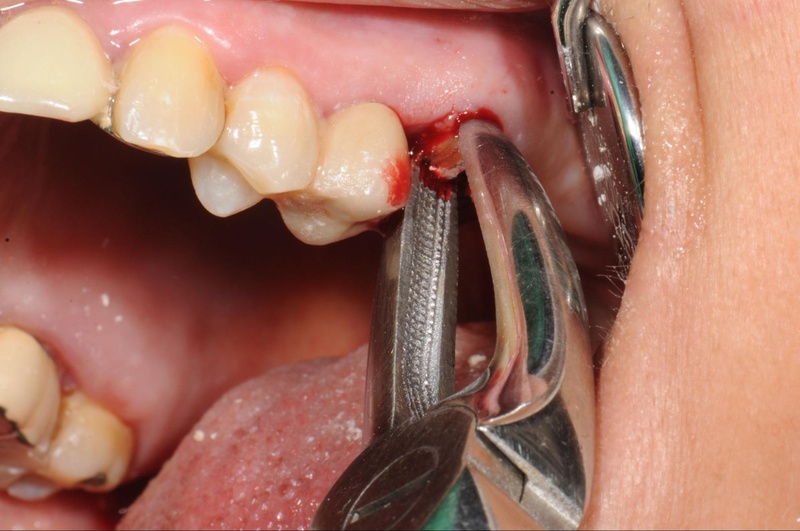

1. Nhổ răng

Nhổ răng thường được chỉ định loại bỏ răng thừa, việc sử dụng máy siêu âm Piezotome sẽ giúp giảm thiểu xâm lấn, tổn thương mô mềm, giúp quá trình nhổ nhẹ nhàng và nhanh phục hồi hơn.

Nhổ răng thừa không gây nguy hiểm ảnh hưởng tới hệ thần kinh trung ương dây thần kinh. Lý do là chúng nằm sâu dưới xương hàm và kết cấu tổ chức răng vững chắc.

Nếu chỉ là nhổ răng đơn giản, quá trình này thường diễn ra trong khoảng 10 – 20 phút. Thời gian này đã bao gồm cả thời gian gây tê.